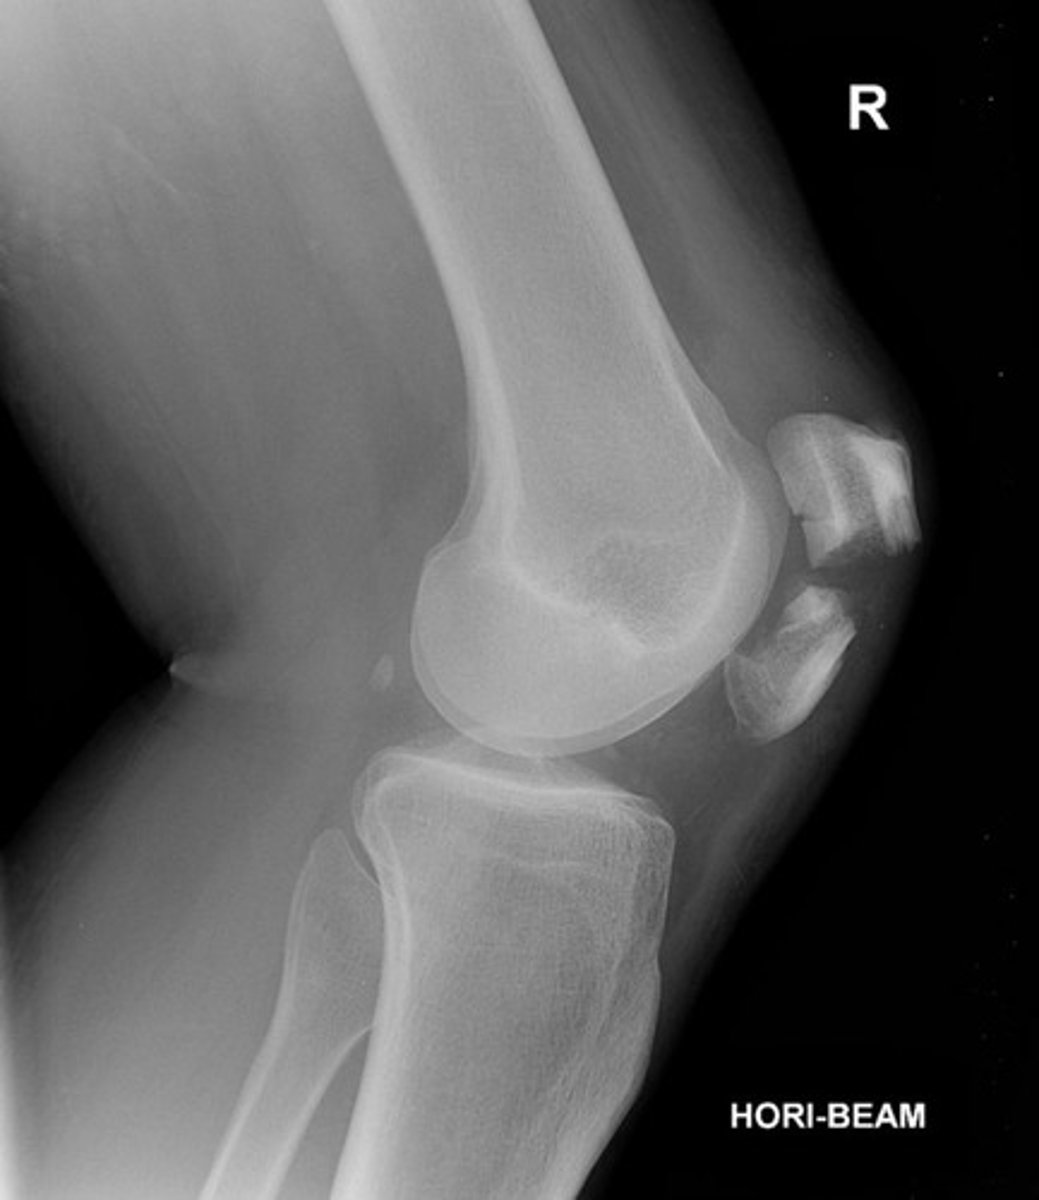

Complete fracture of distal fibula, frequently with fracture of medial malleolus

Pott's fx